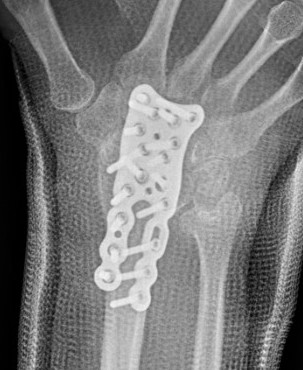

| Stage II | Stage IIIA |

| Sclerosis |

Collapse / fragmentation Normal carpal height |

![]() |